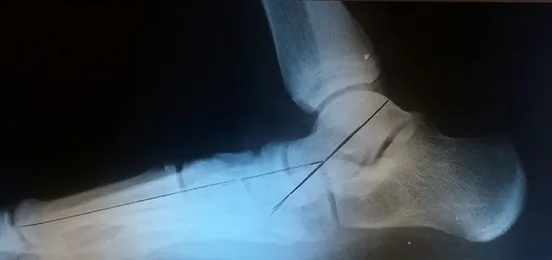

Pre and Postop X-rays Subtalar Joint Implant (Below)

Pre and Postop Subtalar Implant and Percutaneous Achilles Lengthening Below. The first pics show wedging of the distal tibia physis causing ankle valgus due to constant pressure caused by the severity of the flatfoot (JT)